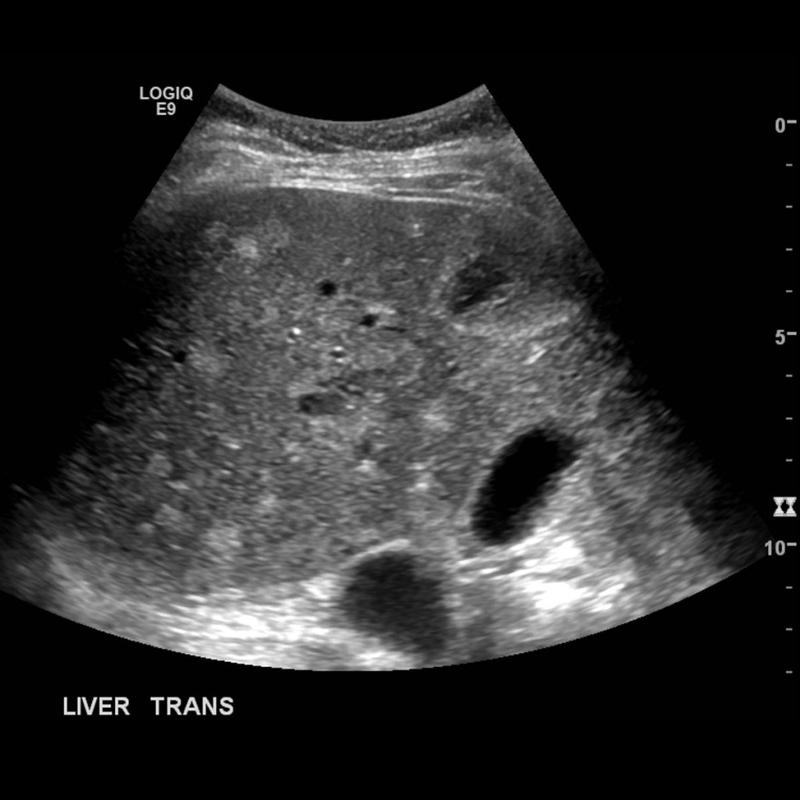

Explain the procedure of a liver exam.

Begin doing a full sweep through the liver. Starting sagittal,

slightly to the left of midline. Change to a transverse view and sweep

up and down the left lobe from a subcostal approach. Look in

transverse through the right lobe subcostally or

intercostally.

Explain the Transverse plane for the liver exam.

The transducer should be angled in a steep cephalic direction to be as parallel to the diaphragm as possible. The transverse plan allows images of liver parenchyma, vascularity and ductal structures.